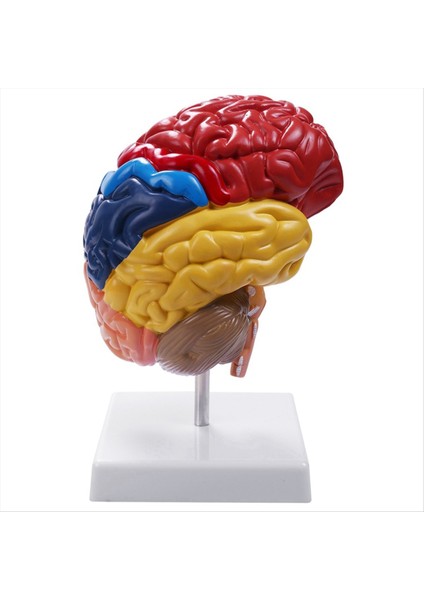

Luminnaly Beyin Anatomik Modeli Anatomisi 1:1 Yarım Beyin Beyin Sapı (Yurt Dışından)

Beyin Anatomik Modeli Anatomisi 1:1 Yarım Beyin Beyin Sapı (Yurt Dışından)

Açıklama: 1:1 Yarım Kesit Beyin Sapı Modeli, Okul Çalışma Ekranı için Renkli Beyin Fonksiyonel Alanı ile birlikte gelir. Beynin yapısını daha iyi anlamanızı sağlayan bir ekran tabanı ile birlikte gelir. Okul öğretim aracı, öğrenme ekranı ve koleksiyonluk eşyalar için harikadır, ayrıca laboratuvar malzemelerinize de harika bir katkı olacaktır. Malzeme: PVC Renk: renkli Paket İçeriği: 1 x Parça Yarım Beyin Modeli Sadece yukarıdaki paket içeriği, diğer ürünler dahil değildir. Not: Işık yansıması ve farklı ekranlar, resimdeki öğenin renginin gerçek olandan biraz farklı olmasına neden olabilir. Ölçümde izin verilen hata +/- 1-3 cm'dir.Ürün özellikleri